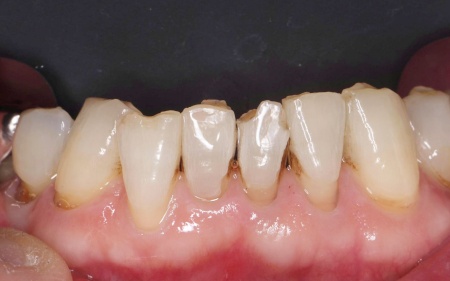

60代女性 すり減った前歯をセラミックのラミネートベニアで修復した症例

拝見したところ、下中央の前歯2本に長年の使用による色の変化やすり減り、小さな欠けが見られました。

すり減った部分は表面がざらつきやすくそこに着色が付きやすくなるため、患者様の場合も削れている部分が茶色く変色していました。